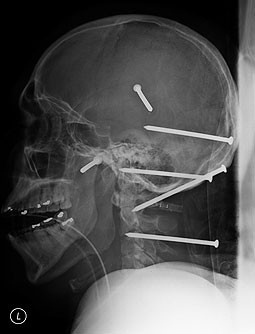

RADIOGRAFII SOCANTE! Bradut in plaman, ciocane in anus si cutite in cap!

Cazuri uimitoare care au socat intreaga lume medicala arata inca o data cat de norocosi sunt unii oameni! De la braduti crescuti in plamani si pana la ciocane introduse in anus, radiografiile sunt ca o harta alb-negru a inventivitatii oamenilor.

(Poza 1)Asa ca incepem "calatoria" noastra cu barbatul din Olt, care a vrut sa scape de constipatie introducandu-si doua ciocane in anus! Desi cazul i-a socat pe medici, barbatul a declarat cu mandrie: "Cu grija, puteam sa bag si mai multe ciocane!!!"